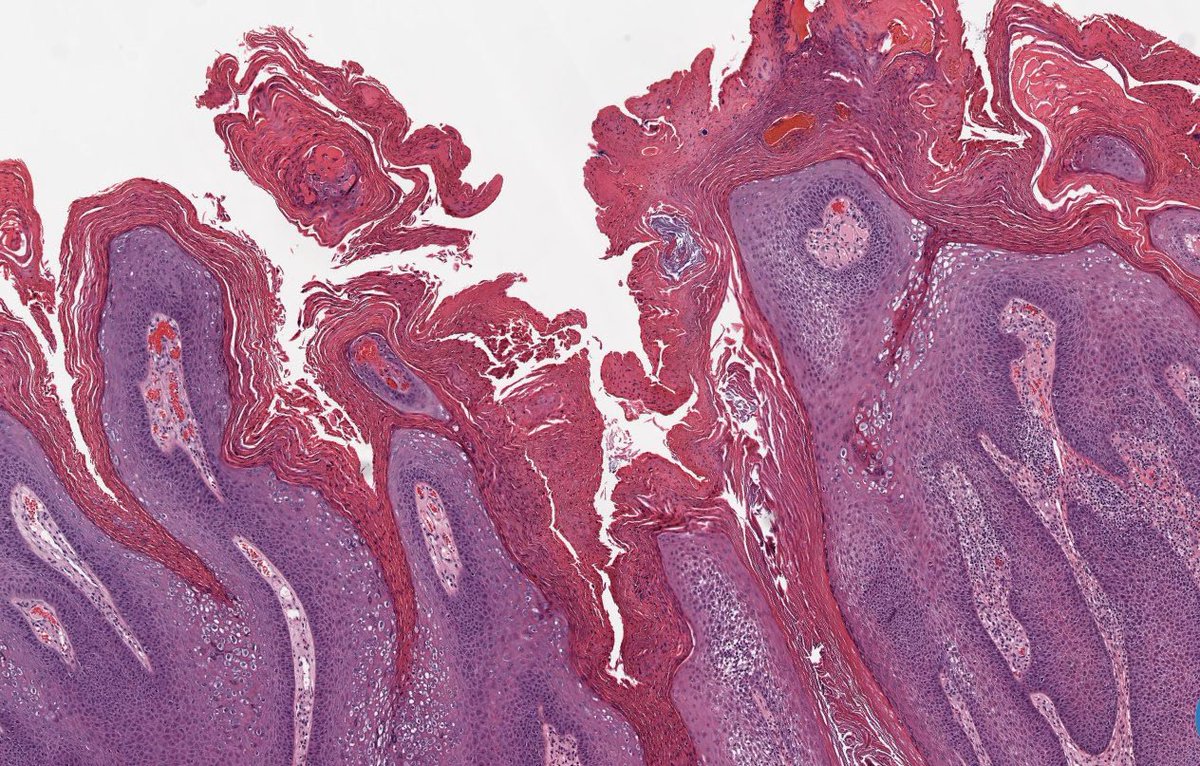

🩸 Talon Noir 📖 Benign ⚾️ 🏀 🏈 ⚽️ Often seen in athletes 🩺 Brown-black macules on foot, most commonly on heel ⚠️ May mimic melanoma 🔬 Acral skin, hyperkeratosis, hemorrhage in stratum corneum +/- telangiectatic vessels in papillary dermis #dermpath #fammed #path4people

Path4People's tweet image. 🩸 Talon Noir

📖 Benign

⚾️ 🏀 🏈 ⚽️ Often seen in athletes

🩺 Brown-black macules on foot, most commonly on heel

⚠️ May mimic melanoma

🔬  Acral skin, hyperkeratosis, hemorrhage in stratum corneum +/- telangiectatic vessels in papillary dermis